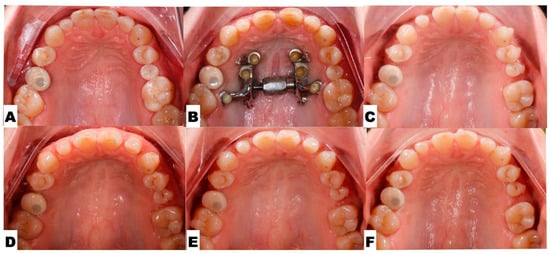

2. Materials and Methods

2.1. Pre-Treatment Records and Analysis

2.2. Pre-Treatment Diagnosis

2.3.4. Postoperative Assessment, Outcome Analysis, and Asymmetry Correction

2.4. Pre-Restorative Records

3. Results